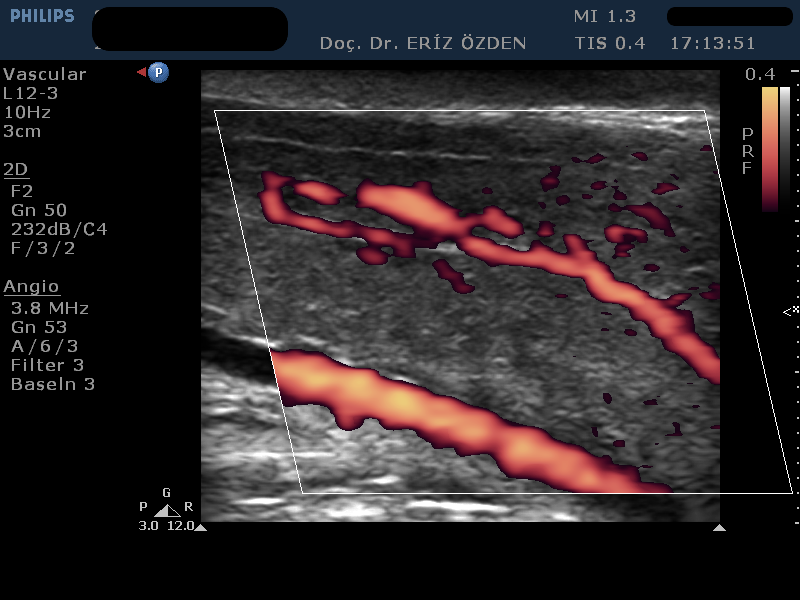

Penil Doppler Nedir? Bu incelemenin tam adı Penil Renkli Doppler Ultrason’dur. Orta ve ileri yaştaki erkeklerde daha sık görülmekle birlikte, bazen genç erkeklerde bile ereksiyon bozukluğu, yani peniste sertleşme yetersizliği görülebilir. Yetersiz sertleşme uzun süre sigara içmiş, yüksek tansiyon ya da şeker hastası erkeklerde daha sık görülen bir rahatsızlıktır. Erektil disfonksiyon adı verilen penisteki sertleşme yetersizliği farklı nedenlere bağlı olarak ortaya çıkabilir. Genç erkeklerde (40 yaş altında) en sık izlenen psikolojik nedenli sertleme bozukluğudur. Daha ileri yaştaki erkeklerde ise testosteron düşüklüğü, atardamarlarda darlık ya da toplardamar yetersizliği nedeniyle yetersiz sertleşme oluşabilir. Penil Doppler tetkikinde, penisin atar ve toplardamarları incelenir. Bu damarların genişliği, damar içinde akan kanın hızı ve penise pompalanan kanın içeride tutulup tutulamadığına bakılır. Böylece, damarsal bir rahatsizlık varsa, tanısı konulmuş olur.

Penil Doppler’de Hangi Ölçümler Yapılır? Normal Değerleri Nedir? Penil Doppler’de atardamardan penis içine akan kanın hızının 35 cm/sn değerinin üzerinde olması gerekir. Ayrıca toplardamarda da kaçak olmamalı, içeri giren kan, penis içinde tutulabilmelidir. Buna end diastolik hız adı verilir ve 0 değerine inmesi, terc,hen ters yönlü akım olarak görülemsi istenir. Bu damar ölçümleri, ilaç verilmesindne önce başlayıp, ilaç verildikten sonra da 30 dakika sürecek şekilde devamlı alınır. Böylece kan akımının dakikalar içindeki değişimi takip edilir. Atardamarların ilaç öncesi ve sonrasındaki çapları da ölçülerek sonuç raporuna yazılır. Ayrıca, sertlik oluştuktan sonra peniste eğrilik gelişirse bunun ölçümleri yapılır. Ek olarak, penisin sertlik derecesi, en sert olduğu andaki uzunluğu ve çapı da ölçülür. Tüm bu ölçüler yazılı raporda belirtilir ve Üroloji doktorunuzun tedavi yöntemini belirlemesinde yön gösterici olur.